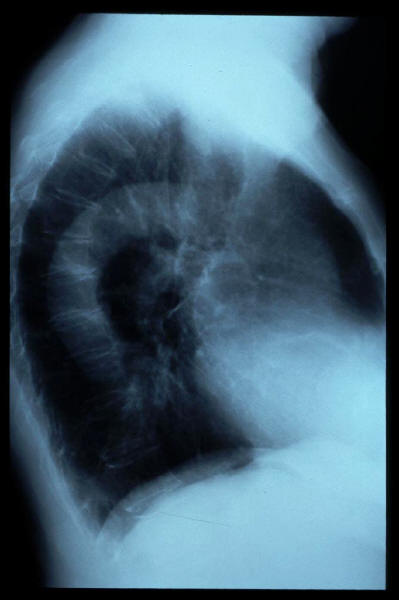

Aerofagia en TEGD.

Aerofagia en TGED.

Dilatación gástrica.

Diverticulosis de colon.

Diverticulosis de colon. Megacolon.

Dolico-megacolon.

E. Steinert. colon descendente en abdomen simple.

E. Steinert. dilatación de colon descendente. abdomen simple.